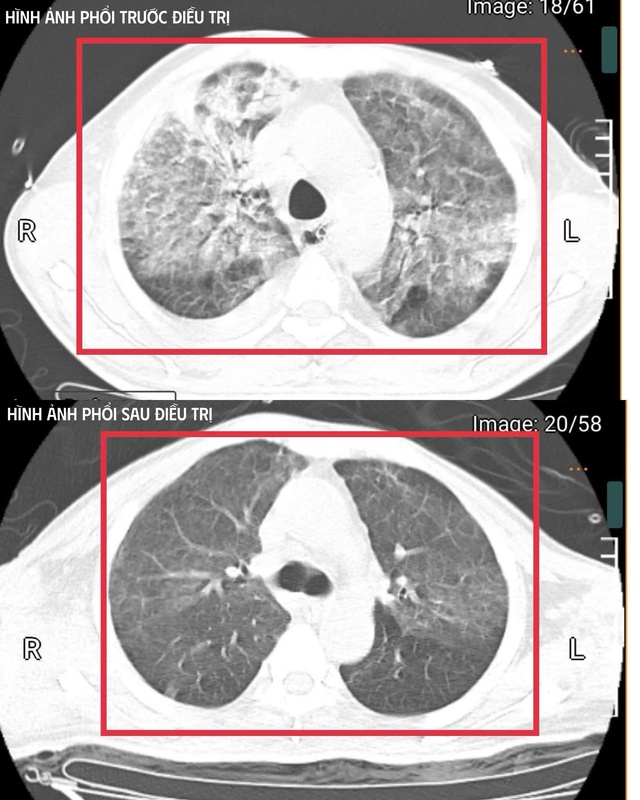

Hình ảnh chụp phổi của bệnh nhân mắc Whitmore. Ảnh: BVCC

Sau ba tuần điều trị, bệnh nhân đã hồi phục hoàn toàn: tỉnh táo, tự thở khí phòng, huyết áp ổn định, cơ lực chi trên đạt 5/5, chi dưới 4/5.

Bệnh nhân được cai máy thở (qua mở khí quản), tập hô hấp tự nhiên và phục hồi vận động. Sau ba tuần điều trị, bệnh nhân đã hồi phục hoàn toàn: tỉnh táo, tự thở khí phòng, huyết áp ổn định, cơ lực chi trên đạt 5/5, chi dưới 4/5. Bệnh nhân được xuất viện và tiếp tục theo dõi ngoại trú.